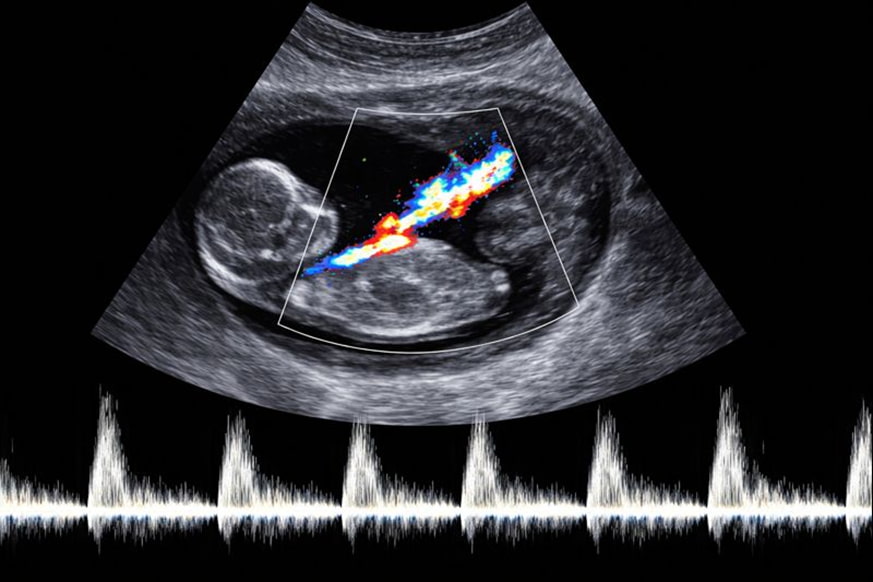

Маточно-плацентарный кровоток жизненно необходим плоду, чтобы получить возможность взаимодействовать с организмом матери, получать кислород и прочие важные вещества. Если процесс проходит с нарушениями, ребенок страдает от удушья и плохо набирает вес. Определить причину проблемы помогает ультразвуковое исследование — допплерография. Во время процедуры доктор определит, насколько интенсивен маточно-плацентарный кровоток, и найдет все возможные патологии.

По ходу процедуры врач использует специальный прибор — допплер, поэтому другое название процедуры — допплерография. С помощью датчика отслеживается кровоток в:

- матке;

- пуповинной артерии;

- плаценте.

Грамотно проведенная допплерография определяет, получает ли плод достаточно кислорода и питательных веществ. Ультразвуковое исследование показывает интенсивность циркуляции крови и любые сосудистые проблемы, замедляющие кровоток в области матки.